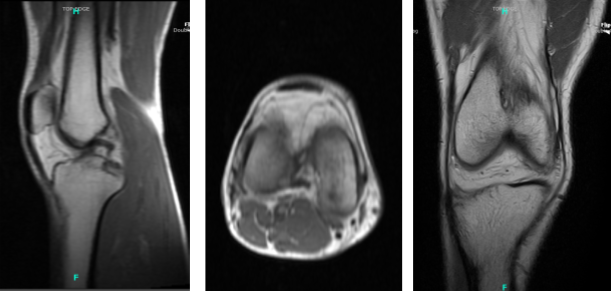

The patient is a 40-year-old male who came into the office after being involved in a car accident. He attempted conservative care, such as physical therapy and anti-inflammatory drugs, but these were ineffective. An MRI revealed an osteochondral defect of the lateral femoral condyle.

MRI Right knee non-contrast

A grade 1 to grade 2 osteochondral lesion of the medial femoral condyle was discovered during an examination of the medial tibiofemoral compartment. A spinal needle and blade were used to create a medial entrance hole. The osteochondral lesion was debrided to stable margins using a shaver.

Further inspection revealed neither medial or lateral meniscus tears. The ACL was not torn. A thorough inspection of the lateral femoral condyle revealed no free cartilage fragments. The osteochondral lesion appeared to be stable and was left alone.